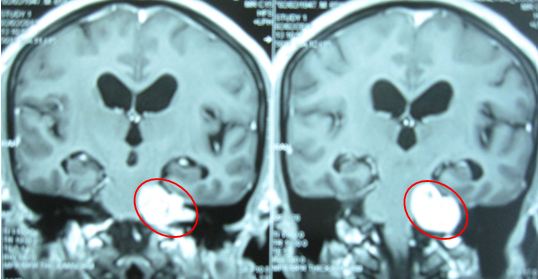

Trường hợp 3: Bệnh nhân nam, 33 tuổi. Được chẩn đoán là u dây thần kinh số VIII bên trái, có các triệu chứng đau đầu, tê mặt trước điều trị. Bệnh nhân được xạ phẫu bằng dao gamma quay liều 13 Gy. Sau xạ phẫu 1 năm: kích thước u thu nhỏ (hình 2.8), các triệu chứng lâm sàng đều cải thiện tốt: hết đau đầu, không tê mặt, không liệt mặt.

Trước điều trị: u dây VIII bên trái kích thước 3,2x2,5cm.

Sau điều trị 1 năm: u thu nhỏ kích thước 1,8x2cm

Hình 4: Hình ảnh MRI u dây VIII trước và sau xạ phẫu gamma quay